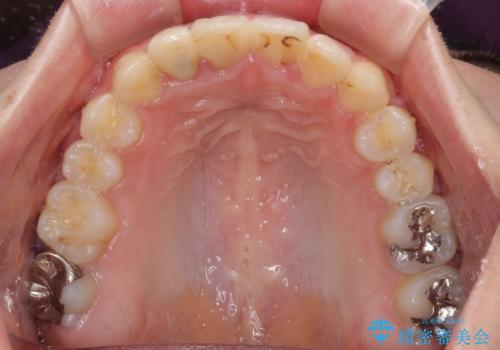

上下の骨幅を改善したことで、スムーズに歯列矯正を行うことができました。

奥歯の咬み合わせを改善する必要があったため、治療は長期化しましたが、きっちりと仕上げることができました。